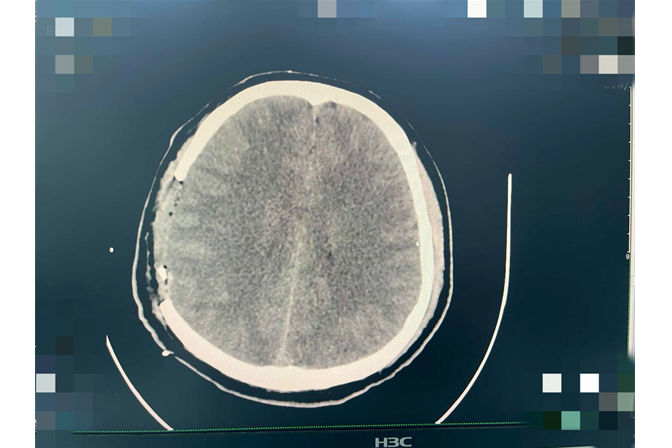

手术后的影像

术后的恢复之路,同样充满挑战。医护团队在小龙颅内压稳定、生命体征平稳后,第一时间启动床旁康复治疗——从被动活动僵硬的左侧肢体以预防关节挛缩,到指导主动抓握训练、辅助翻身,再到搀扶进行站立平衡训练,每一个细微的进步,都凝聚着医护人员的心血。得益于他年轻、身体基础条件较好,再加上医护人员的专业治疗与护理,小龙的恢复速度超出预期——术后仅17天,便能在辅助下下床活动,8月19日出院那天,他自己拎着行李,左手能熟练地拉开病房门,连医生都说“这么严重的出血,恢复得这么快,真是少见”。